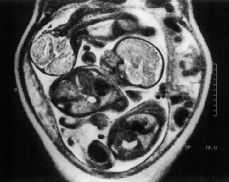

La RM confirmó todos los hallazgos de los US como se detalla en la tabla 2, permitiendo además descubrir otros no detectados por ecografía. En el caso número 3, higroma quístico en gestación de 21 semanas, la RM permitió visualizar edema del dorso de las manos, de los pies y de la región pretibial (Fig. 1), no visualizados mediante ecografía, hallazgos muy sugestivos de Síndrome Turner confirmándose en el estudio del cariotipo fetal. En el caso número 4, hidrocefalia y pies equinovaros, la RM visualizo además una hipoplasia del cerebelo (Fig. 2), confirmada en la necropsia. En el caso número 5, gestación gemelar y presencia de hydrops fetal severo de uno de los fetos, a pesar de un estudio incompleto de la RM por un síndrome supino hipotensor materno, puso de manifiesto una alteración en la imagen del líquido amniótico del segundo feto, hallazgo sugestivo de sangrado o presencia de meconio. En el caso número 8, la RM permitió el diagnóstico de hernia diafragmática al visualizar los diafragmas y la disposición de los órganos toracoabdominales (Fig. 3). El estudio postnatal confirmó el diagnóstico. En un oligoamnios severo por RPM a las 33 semanas, caso número 9, el examen mediante US detectó un mielomeningocele lumbar, hallazgos confirmados por la RM, permitiendo un examen detallado de la anatomía fetal a pesar de la ausencia de líquido amniótico y la detección de un síndrome de Arnold Chiari tipo II no detectado por ecografía. Por último en el caso número 13, gestación de 33 semanas con desplazamiento cardíaco, la RM evidenció un arco aórtico derecho (Fig. 4), no visualizado por US, sugestivo de cardiopatía, estando pendiente de estudio postnatal al no haber finalizado aún el embarazo.

Figura 1.Higroma qustico correspondiente a un sndrome de Turner. Gestacin de 22 semanas. Imagen coronal fetal. Edema del dorso de la mano (flecha). Edemas pretibial y del pie (puntas de flecha). Globo ocular (flecha gruesa).

Figura 2.Hidrocefalia en la 22 semanas de gestacin. Imagen sagital fetal. Dilatacin ventrculo lateral (flecha larga). Hipoplasia del cerebelo (punta de flecha). Pies equinovaros (flecha corta).